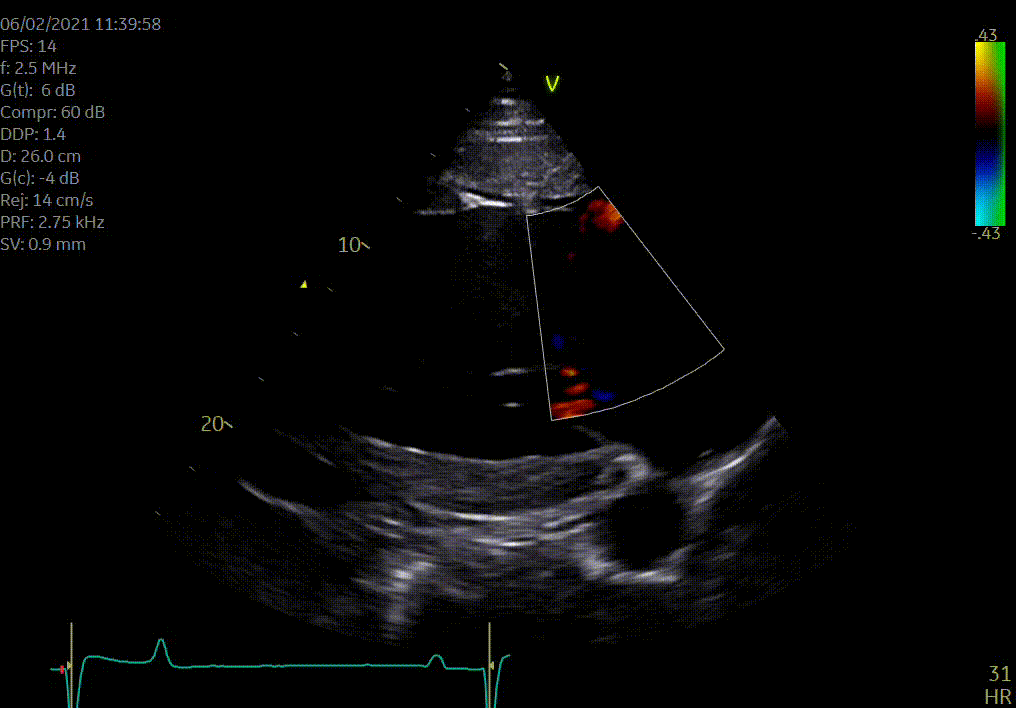

Heeft uw paard een hartruis? Dan is het aanbevolen om een echocardiografie (hartonderzoek) en een inspanningstest met elektrocardiogram (EKG) te laten uitvoeren. Zo kunnen we beoordelen of het veilig is om uw paard te berijden. Een hartruis is namelijk niet altijd een probleem. Met een echocardiografie onderzoeken we of het hart een normale structuur en werking heeft en bepalen we de ernst van eventuele klepafwijkingen.

Voor een uitgebreid hartonderzoek hoeft u niet langer naar een kliniek. Zowel de echocardiografie als de inspanningstest met elektrocardiogram kunnen eenvoudig bij u ter plaatse worden uitgevoerd.

Wij voeren hartonderzoeken uit op locatie in heel België, Nederland, Frankrijk, Duitsland en Luxemburg.

Hartonderzoek - Echocardiografie - Electrocardiografie (EKG)